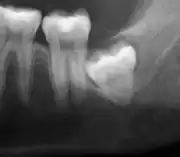

Impacted wisdom teeth are classified by their direction of impaction, their depth compared to the biting surface of adjacent teeth and the amount of the tooth's crown that extends through gum tissue or bone. Impacted wisdom teeth can also be classified by the presence or absence of symptoms and disease. Screening for the presence of wisdom teeth often begins in late adolescence when a partially developed tooth may become impacted. Screening commonly includes a clinical examination as well as x-rays such as panoramic radiographs.

Impacted wisdom teeth are classified by the direction and depth of impaction, the amount of available space for tooth eruption, and the amount of soft tissue or bone (or both) that covers them. The classification structure helps clinicians estimate the risks for impaction, infections and complications associated with wisdom teeth removal.[6] Wisdom teeth are also classified by the presence (or absence) of symptoms and disease.[7]

Impacted wisdom teeth are often described by the direction of their impaction (forward tilting, or mesioangular being the most common), the depth of impaction and the age of the patient as well as other factors such as pre-existing infection or the presence of pathology (cysts, tumors or other disease).[5]: 143–144 Each of these factors is used to predict the difficulty (and rate of complications) when removing an impacted tooth, with age being the most reliable predictor[8] rather than the orientation of the impaction.[9]

The diagnosis of impaction can be made clinically if enough of the wisdom tooth is visible to determine its angulation, depth, and if the patient is old enough that further eruption or uprighting is unlikely. Wisdom teeth continue to move to the age of 25 years old due to eruption, and then continue some later movement owing to periodontal disease.[18]

If the tooth cannot be assessed with clinical exam alone, the diagnosis is made using either a panoramic radiograph or cone-beam CT. Where unerupted wisdom teeth still have eruption potential several predictors are used to determine the chance of the teeth becoming impacted. The ratio of space between the tooth crown length and the amount of space available, the angle of the teeth compared to the other teeth are the two most commonly used predictors, with the space ratio being the most accurate. Despite the capacity for movement into early adulthood, the likelihood that the tooth will become impacted can be predicted when the ratio of space available to the length of the crown of the tooth is under 1.[5]: 141